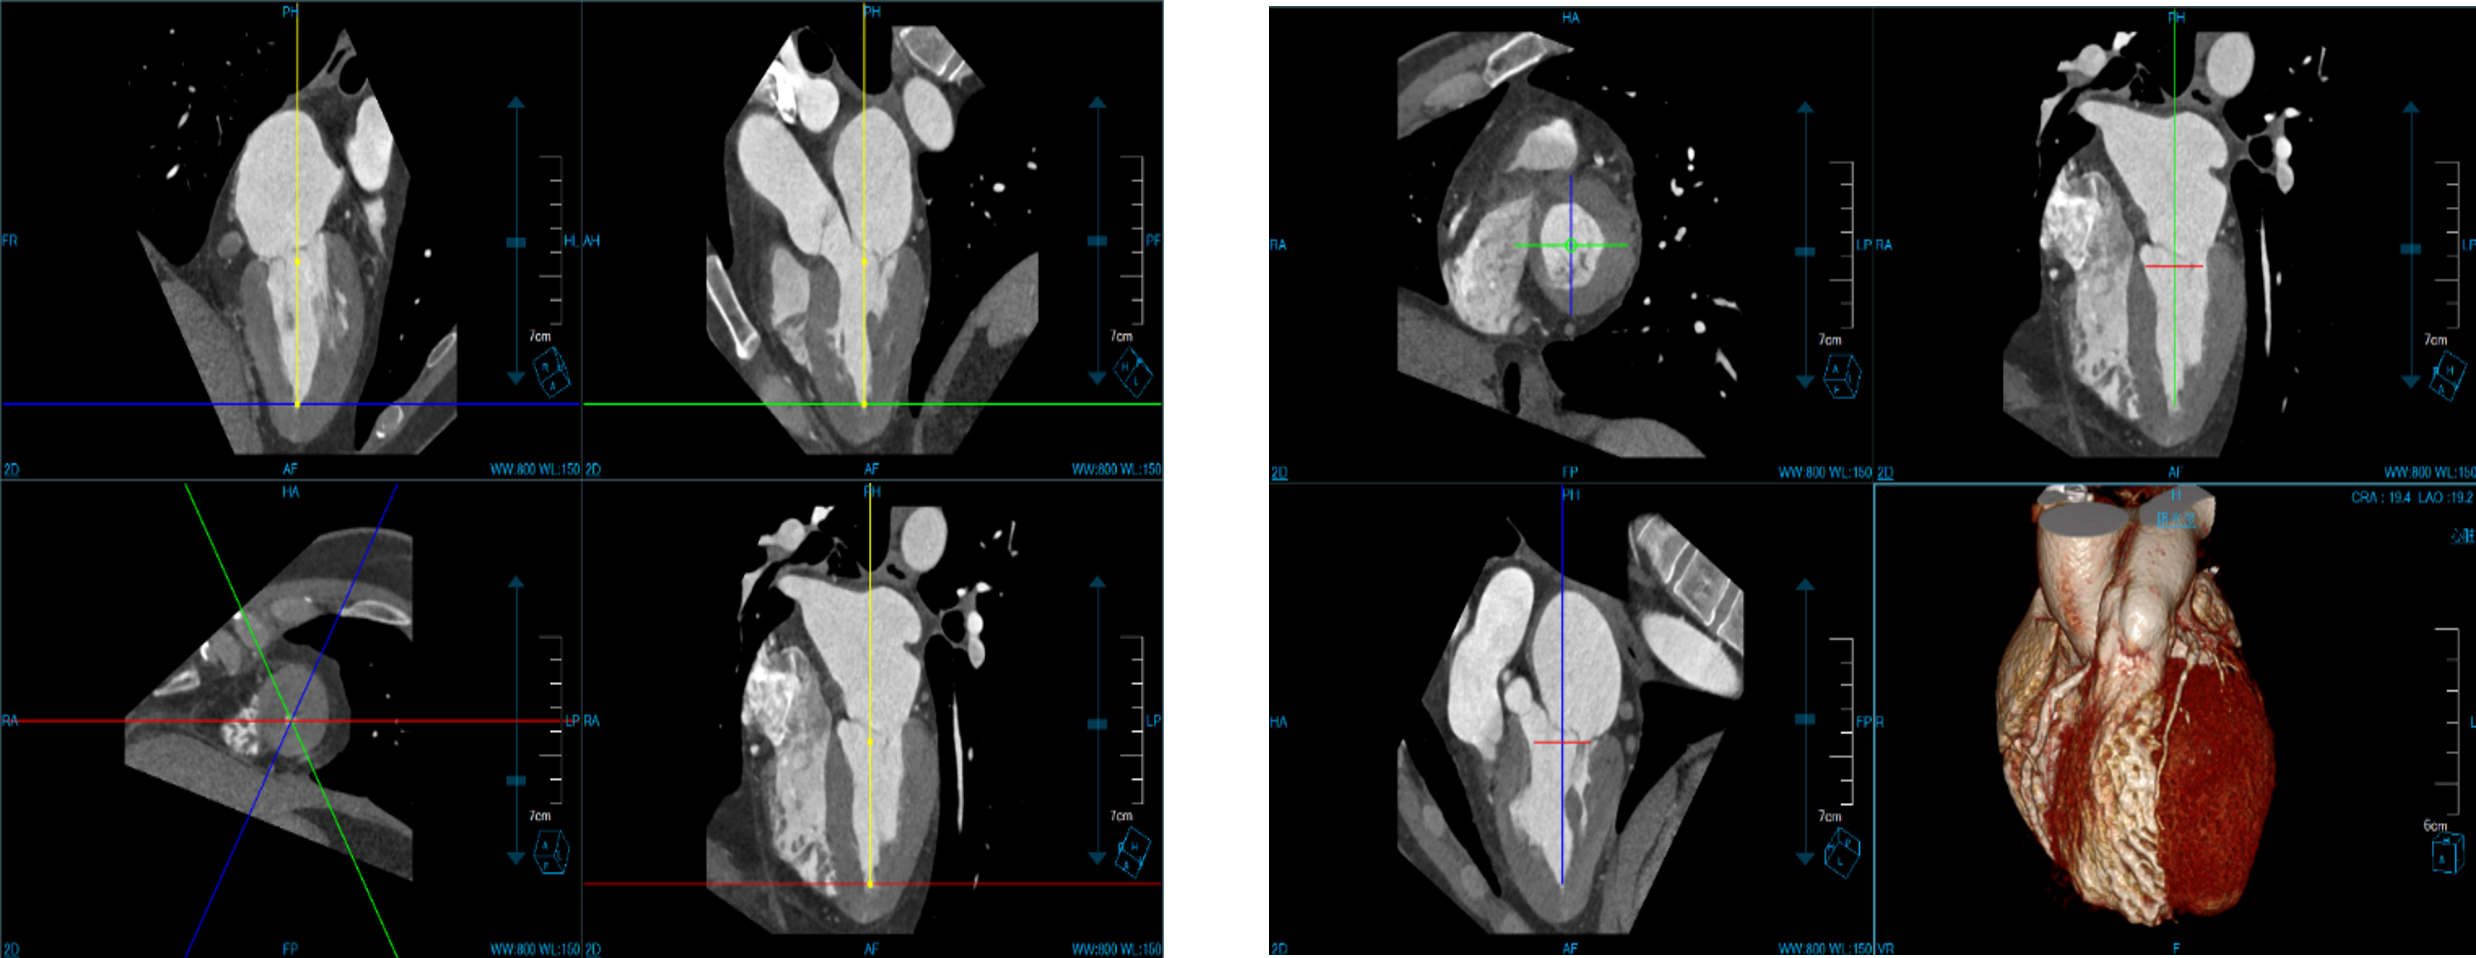

Cardiac Viewer Images

View heart images of each phase, execute three-dimensional reconstruction and heart extracted for CT heart images, and then view patient heart by more intuitive way, diagnosis various cardiovascular diseases.

• Different phases data comparison

• 4D play

• Oblique MPR display

Cardiac Function Analysis

Analyze a variety of heart functions

• Left ventricular volumes Ejection fraction

• Left ventricle wall motion and thickening

• 4D Rendering